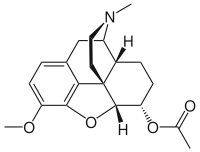

3,6-diesters of morphine

- Acetylpropionylmorphine

- 3,6-Dibutanoylmorphine

- Diacetyldihydromorphine (dihydroheroin, acetylmorphinol)

- Dibutyrylmorphine

- Dibenzoylmorphine (first designer drug)

- Diformylmorphine

- Dipropanoylmorphine

- Heroin (diacetylmorphine)

- Nicomorphine

Structures

| 3,6-diesters of morphine | ||||

|---|---|---|---|---|

Acetylpropionylmorphine Acetylpropionylmorphine |

3,6-Dibutanoylmorphine |  Diacetyldihydromorphine Diacetyldihydromorphine(dihydroheroin, acetylmorphinol) | ||

Dibutyrylmorphine Dibutyrylmorphine |

Dibenzoylmorphine Dibenzoylmorphine |

Diformylmorphine Diformylmorphine | ||

Dipropanoylmorphine Dipropanoylmorphine |

Heroin Heroin(diacetylmorphine) |

Nicomorphine Nicomorphine | ||